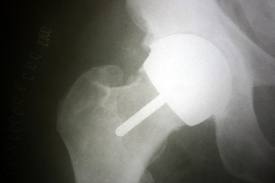

I was almost 55 at the time of I had my right hip resurfaced in 2005 and had it done locally in Plymouth, Devon. Because I had private medical insurance through my employment, I was referred to a surgeon at the local private hospital who suggested that resurfacing would probably be a better option than THR for me as I was still relatively young. Although he made it clear that the procedure was relatively untried at that point in time, he also said he’d done over 24 of the procedures and was very pleased with the results. I’ve never been the sort of person to question or doubt an expert – if he said it would be a good idea, then I was happy with that; I just wanted rid of the arthritic pain and get back to a normal existence. It was not until I found the hipsrus and surfacehippy Yahoo groups while convalescing postoperatively that I discovered this was a very technically demanding procedure and it was advisable to have it done by a surgeon who had performed many more than the 25 or so mine had experience of.

The consultant concerned said my cup angle was not ideal given the state of knowledge in 2008 but that it could have been an X-ray of a hip he himself had done in 2005 – the implication being that my surgeon had not done anything wrong, but rather that knowledge had improved between 2005 and 2008. From what I’ve read more recently, the opinions on ideal angles may have been revised yet again since 2008. The following investigations/procedures were done – ultrasound, aspiration of fluid from the joint and a right psoas tendon steroid injection. The doctor who performed the ultrasound said there was more fluid around the joint than there should be at 3 years, and there was some echogenic material in there (I never managed to get an explanation of what that meant) but I was also told that nothing unexpected had been found. I cannot now remember the colour of the aspirated fluid but I do remember asking about it as it looked alarming to me (not that I knew what it should look like!) and was told that, if metal was present, the fluid would look like it contained coffee grounds, which mine didn’t. The pain gradually subsided over a period of a few weeks.

In the autumn of 2010 I received a letter which was being sent out re the problems being found with some MOM resurfacings. I decided to see my GP and ask for everything to be checked out even though I was going through a relatively good period. He was a bit reluctant to refer me, saying that any problems were seen in the first five years so there probably wasn’t anything wrong. But he did do a referral and I saw a different consultant from the one who did my operation, but at the same private hospital (this time on the NHS as I no longer had private medical insurance). He was also reassuring, but decided to do a blood test, CT scan and MRI scan. He told me that the metal ions in the blood were elevated but that was to be expected, that the MRI scan didn’t show anything and that the CT scan might indicate some loosening of the cup so he wanted to see me again in six months’ time to keep an eye on it. That follow-up visit took place on June 6th 2011 and a couple of X-rays were done before the consultation to check for any evidence of cup loosening.

At the June 6th appointment my consultant told me the X-rays did show quite a steep cup angle but he had other patients with an equally steep angle who were happy. He also said there was no evidence of cup loosening. I discussed with him my concerns but, while he couldn’t give me any particular reason for my symptoms, he didn’t seem to think that I needed to be concerned about metallosis and that I needed to think about whether my symptoms were bad enough to warrant a revision or whether I was better off living with them. He told me a resurfacing revision was difficult and, when I asked, said he had done five. I didn’t ask, but it may be that none of those were for metallosis, and therefore it’s quite possible he’s had no experience at all of revising a hip with damaged surrounding tissues.

From my internet research I was aware of Vicky and her website so, that afternoon, I decided to write to her telling my story as I’ve done here, and ask if she thought my symptoms could be caused by something less potentially damaging than metallosis. She immediately wrote back with an offer to consult with some top surgeons but needed my X-rays and blood results. Because I’d never seen the actual blood results I had to get those sent to me. I sent Vicky the X-rays and a copy of the blood results when they arrived and waited for the response. By Sunday June 12th Vicky had forwarded responses from six surgeons, all of whom said the metal ions in the blood were sky high, the cup angle was too steep, my symptoms indicated metallosis and I needed a revision as soon as possible to prevent further damage.